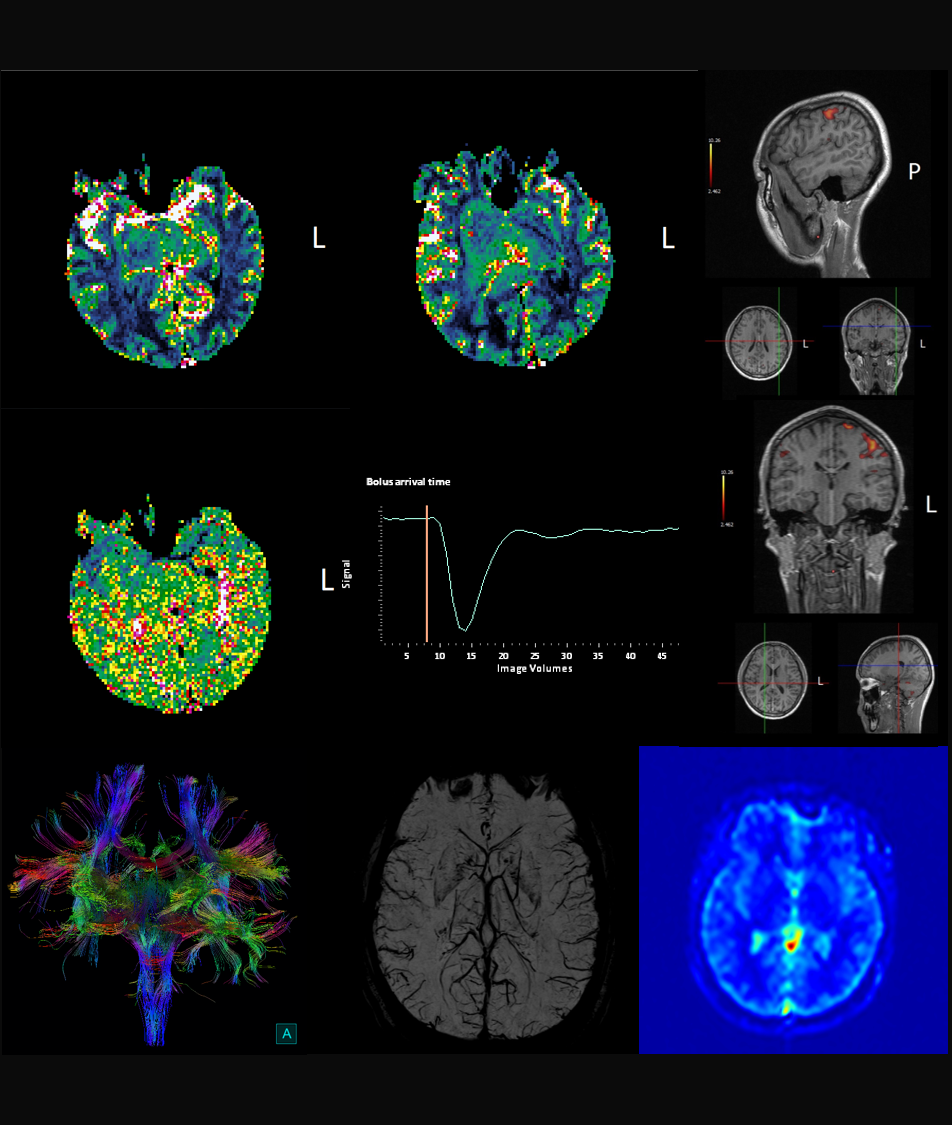

中樞神經-高級臨床應用